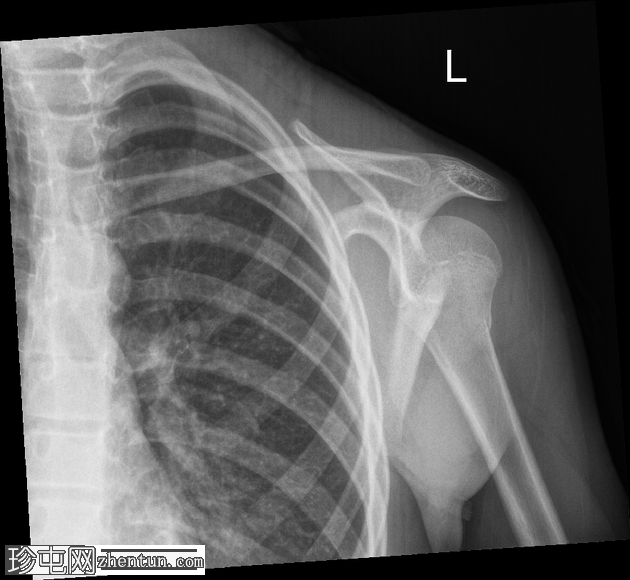

正位片

左侧肱骨近端干骺端可见环状骨折。皮质轮廓轻度不规则,呈环状弯曲,但无明显移位或成角。肱骨头与肩胛盂对位良好。